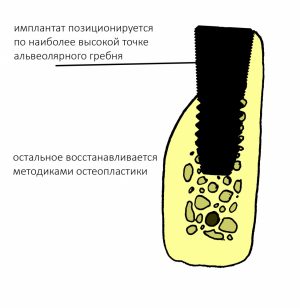

Ок, договорились, что полированные части любого имплантата должны находиться выше уровня костной ткани. В идеальных условиях добиться этого довольно просто. А как быть с неидеальными условиями? Например, при сложном рельефе альвеолярного гребня или немедленной имплантации, если края лунки имеют разную высоту. И вот здесь, как правило, делается большинство ошибок позиционирования по глубине, и начинаются пляски с бубнами.

Итак, сложный рельеф альвеолярного гребня:

На практике:

Обратите внимание, что ортопедическая платформа выставляется по верхней точке альвеолярного гребня, а не по нижней. Недостающий участок альвеолярного гребня восполняется любой методикой остеопластики: